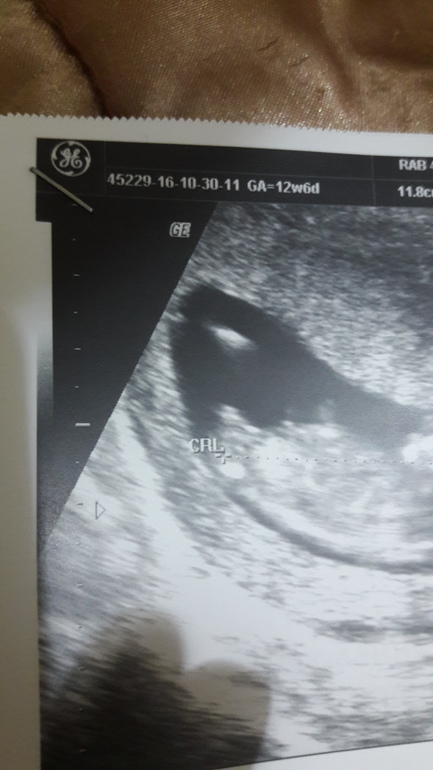

УЗИ, КТГ, доплерПошли внепланово,т.к. муж был выходной и ни разу не был на узи где малышастика видно,только на раннем сроке был где только пя было видно.Очень хотел и всё никак не получалось,ну я решила сделать ему подарок и мы пошли на узи,но нас ожидал еще один сюрприз нам сказала узист (моя ведущая гиня),что ничего не торчит)),склонна к тому,что девочка,но и я почему то уверенна,что у нас Дашенька,сама видела ,что пусто и ничего похожего на мальчика нет)фото правда не очень,на мониторе было видно лучше,но всё же гляньте и вы,что скажете? Это прошлое узи